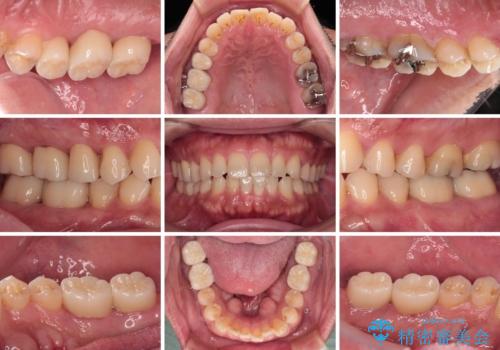

まずは仮歯に置き換え、歯周ポケットを除去するための外科処置(歯肉弁根尖側移動術)を行い、治癒を待ってセラミッククラウンにて補綴治療を行うこととしました。

外科処置後は知覚過敏症状が酷くなることが多いのですが、術後は比較的落ち着いており、スムーズに処置を進めることができました。